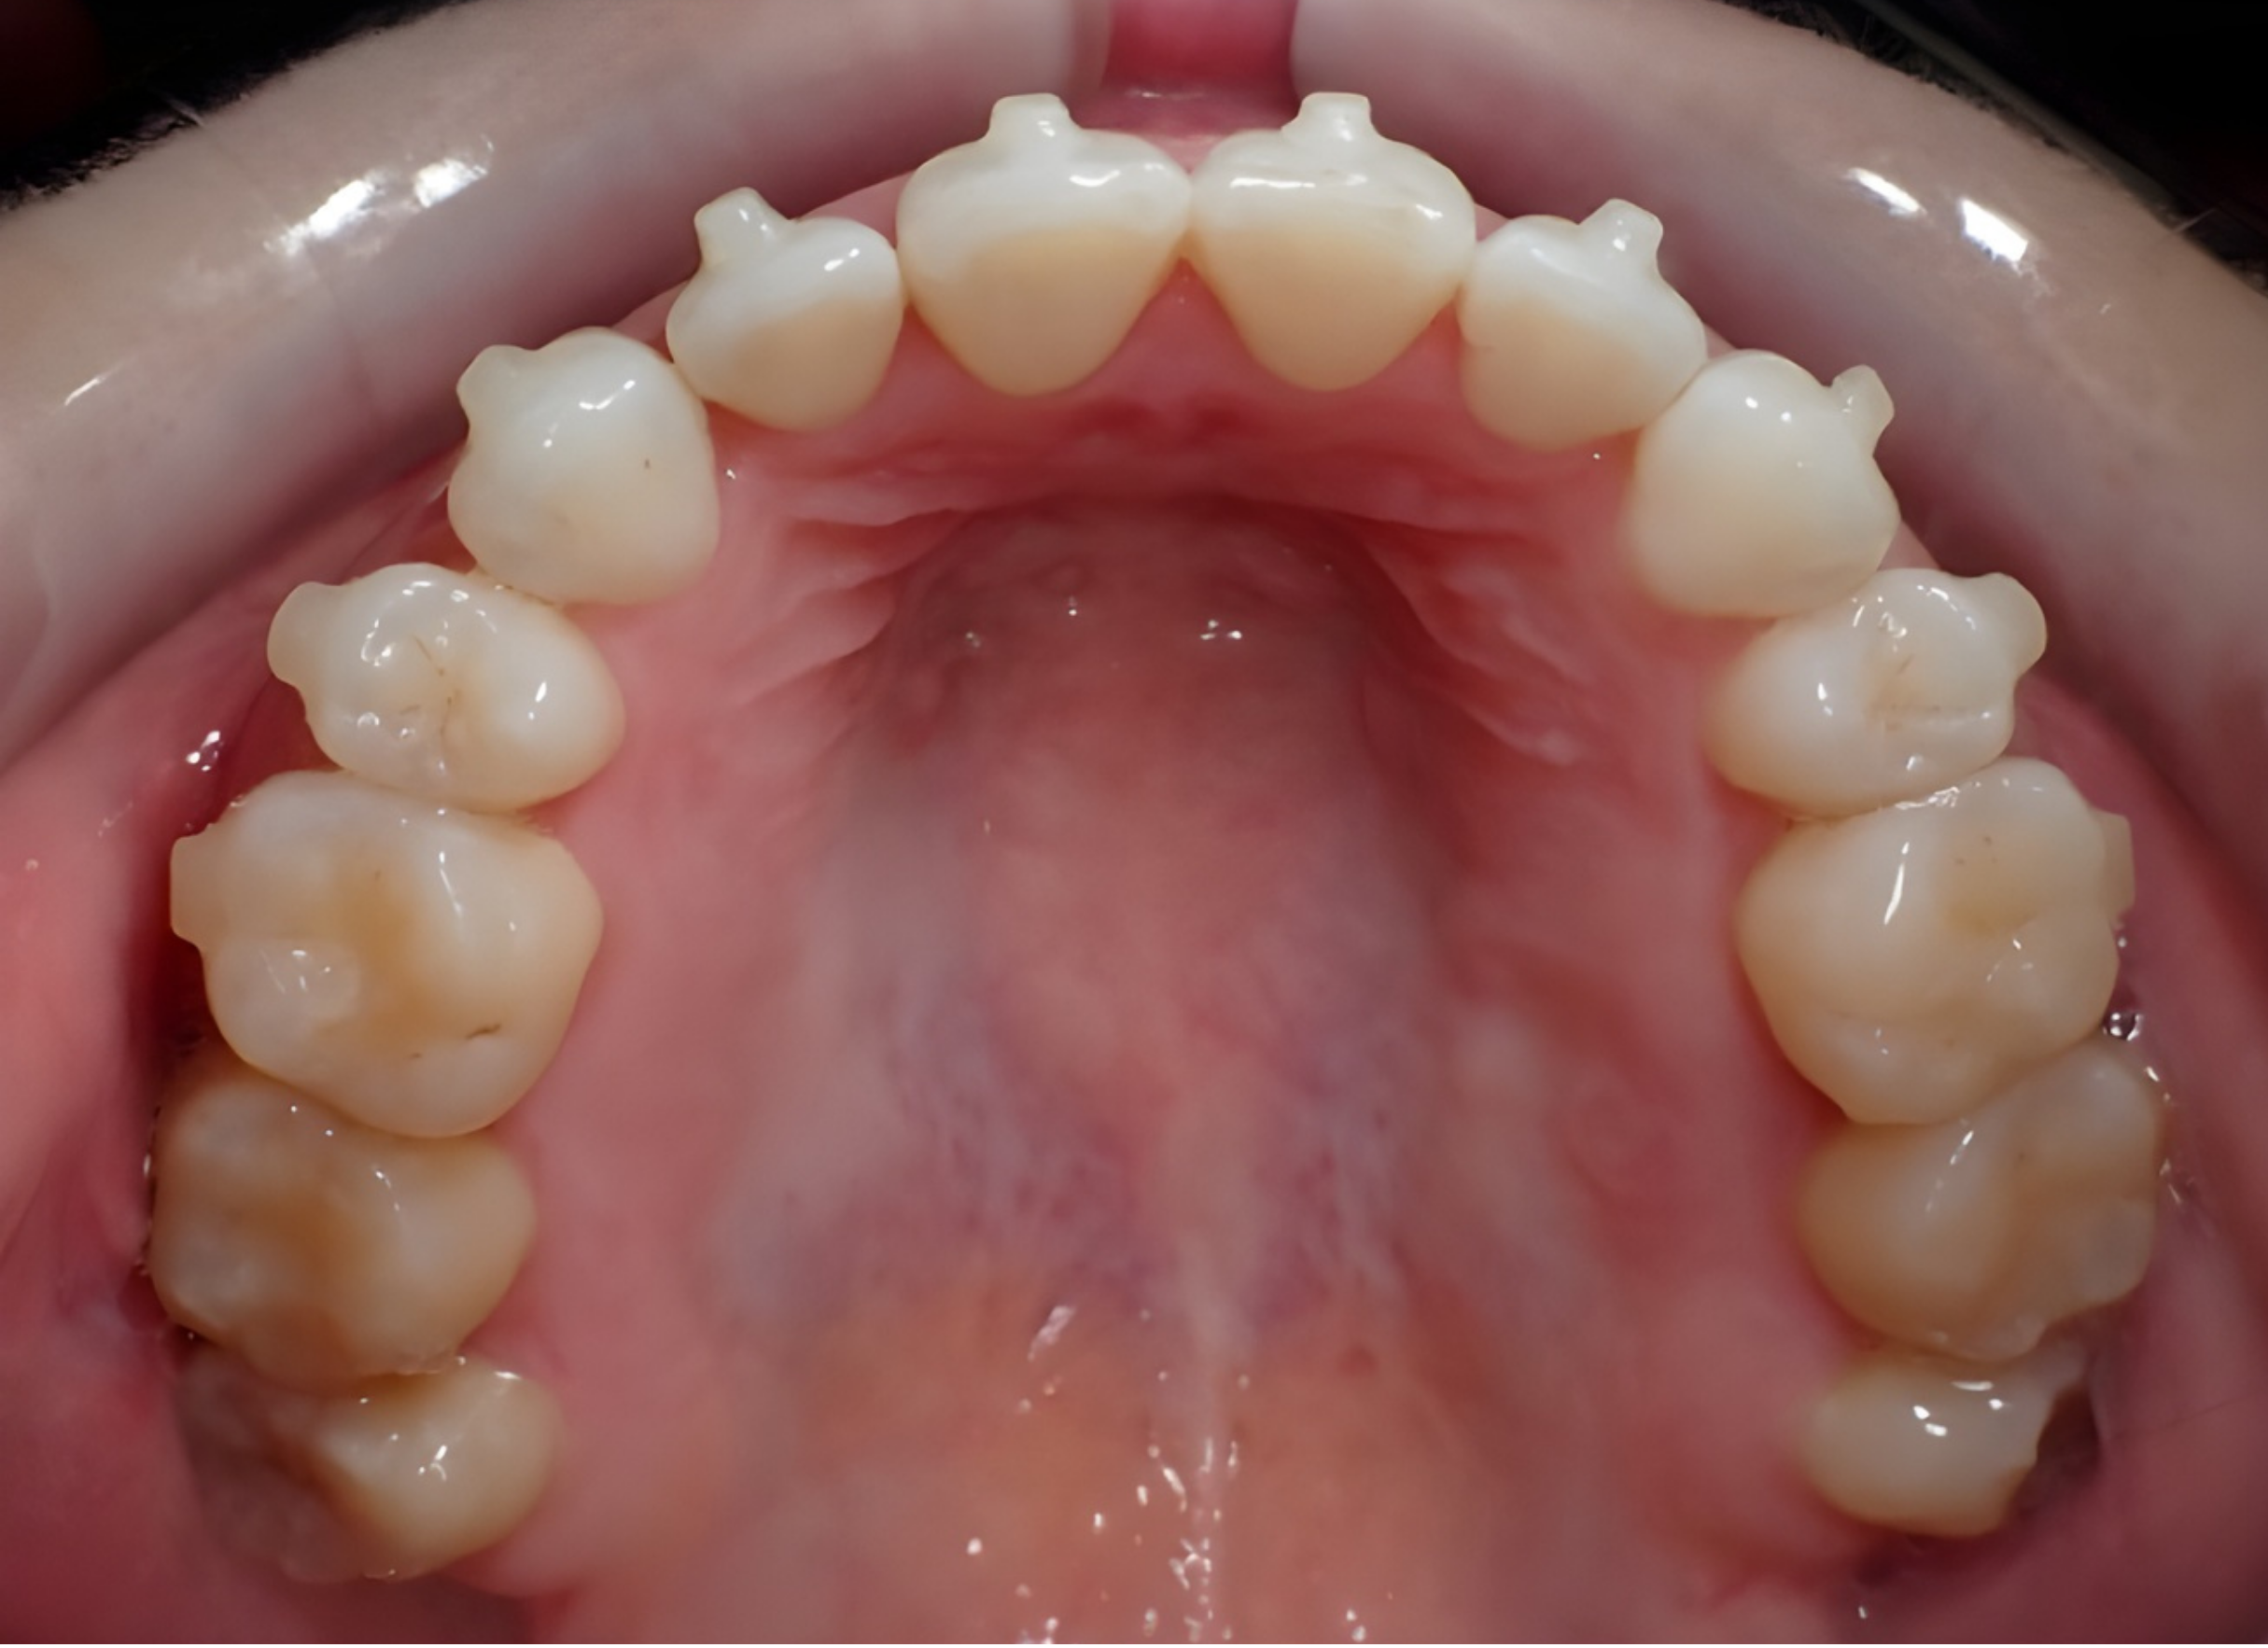

Will I see a gap between my front teeth?

Yes — many patients temporarily develop a small space between the upper front teeth during expansion. This is a normal and positive sign that skeletal expansion is occurring. The gap typically closes naturally or is corrected during orthodontic treatment.

What happens after MARPE treatment?

After expansion stabilizes, orthodontic treatment such as braces or clear aligners is often used to align the teeth and refine the bite. In some cases, your Orthodontist can utilize braces or clear aligners to work simultaneously with the MARPE to minimize the gap that forms.